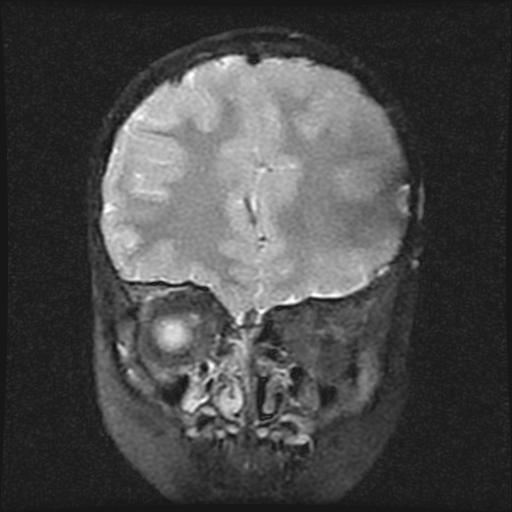

6岁小儿,左侧视神经瘤术后。现左侧视力减退。